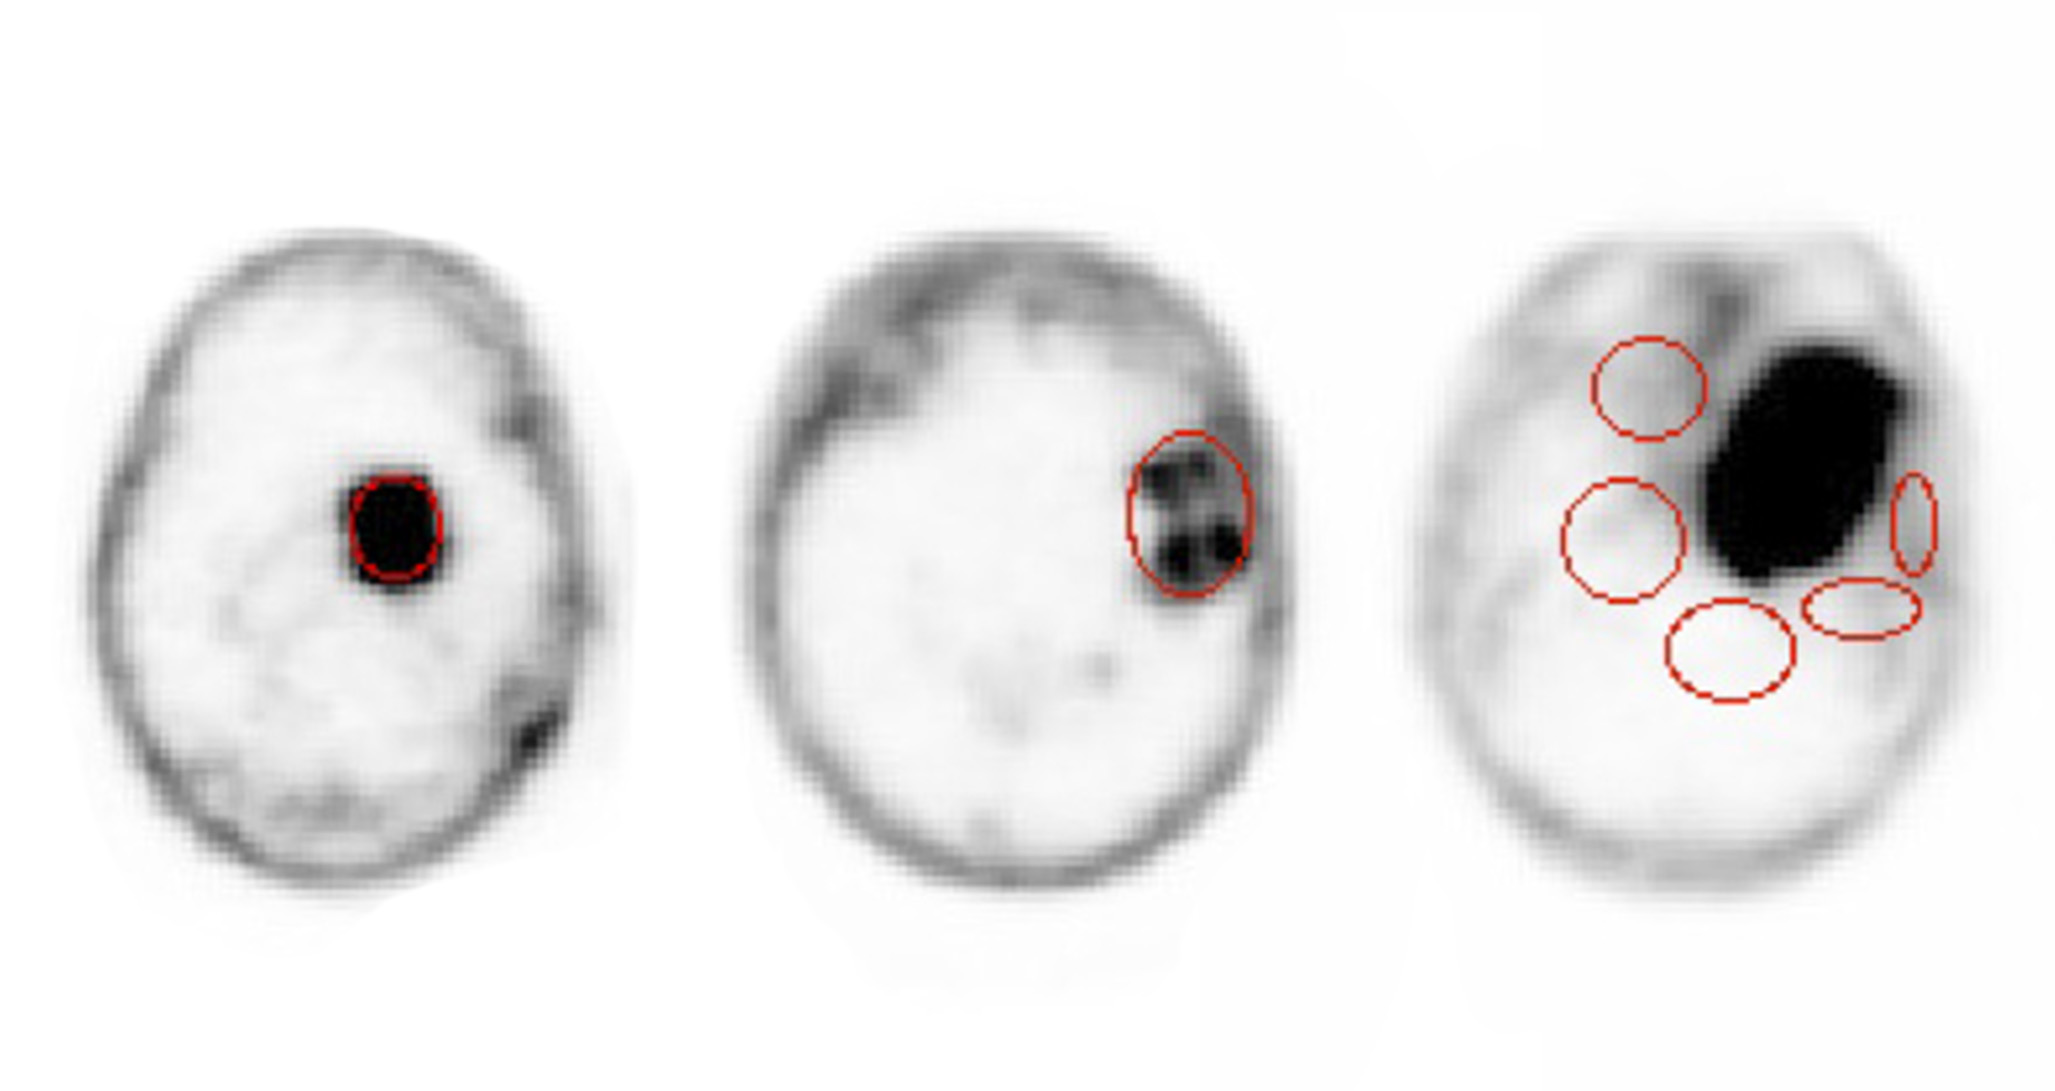

To estimate the mean tumor uptake, for each meningioma patient we considered several slices of the PET scan and in each of it a region of interest (ROI), containing only lesioned tissue on the basis of the CT scans, was defined. In presence of several lesions, each one was considered separately (see Fig. 1 on the left for an example). In the case of the HGG, instead, there was often a necrotic area in between uptaking tissues (center of Fig. 1), due to previous treatments. In such cases a ROI comprehensive of both the uptaking and the interstitial regions was chosen.

As far as the healthy tissue is concerned, several ROIs on several slices of the scan were chosen. Since the βsuperscript𝛽\beta^{-} radiation is local, the ROIs were chosen, by means of the information from the CT, close to the tumor margins, as shown in Fig. 1 (right). In this case, a weighted average was used to evaluate μNTsubscript𝜇𝑁𝑇\mu_{NT}, σNTsubscript𝜎𝑁𝑇\sigma_{NT} and the corresponding SUVNT𝑆𝑈subscript𝑉𝑁𝑇SUV_{NT}.

Refer to caption

Figure 1: Example of ROI definition for meningioma (left), HGG (center), and non-tumor (right).